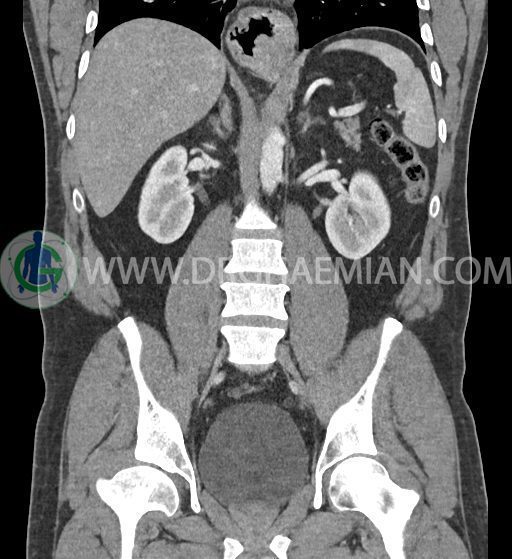

سی تی اسکن شکم و لگن با استفاده از اشعات ایکس تصاویر عرضی از ناحیه شکم و لگن ایجاد میکند. در این کیس فتق هیاتوس و هیدرویورترونفروز دیده می شود.

در سی تی اسکن اسپیرال شکم و لگن با کنتراست خوراکی و وریدی (مولتی دیدکتور 16 با مقاطع ظریف و بازسازی های ساژیتال و کرونال) :

ضایعه ای در کبد، کیسه صفرا، مجاری صفراوی، طحال، کلیه ها، پانکراس و آدرنالها مشهود نیست.

کلیه ها کنتراست را ترشح کرده اند و نمای سیستم پیلوکالیسیل و حالب دو طرف نرمال است .

-sliding hiatal hernia به ابعاد 60x44mm با جابجایی JE.junction و فوندوس معده به فضای مدیاستن خلفی دیده می شود.

-هیدرویورترونفروز جزئی دو طرفه دیده می شود که می تواند ثانویه به اتساع مثانه باشد.